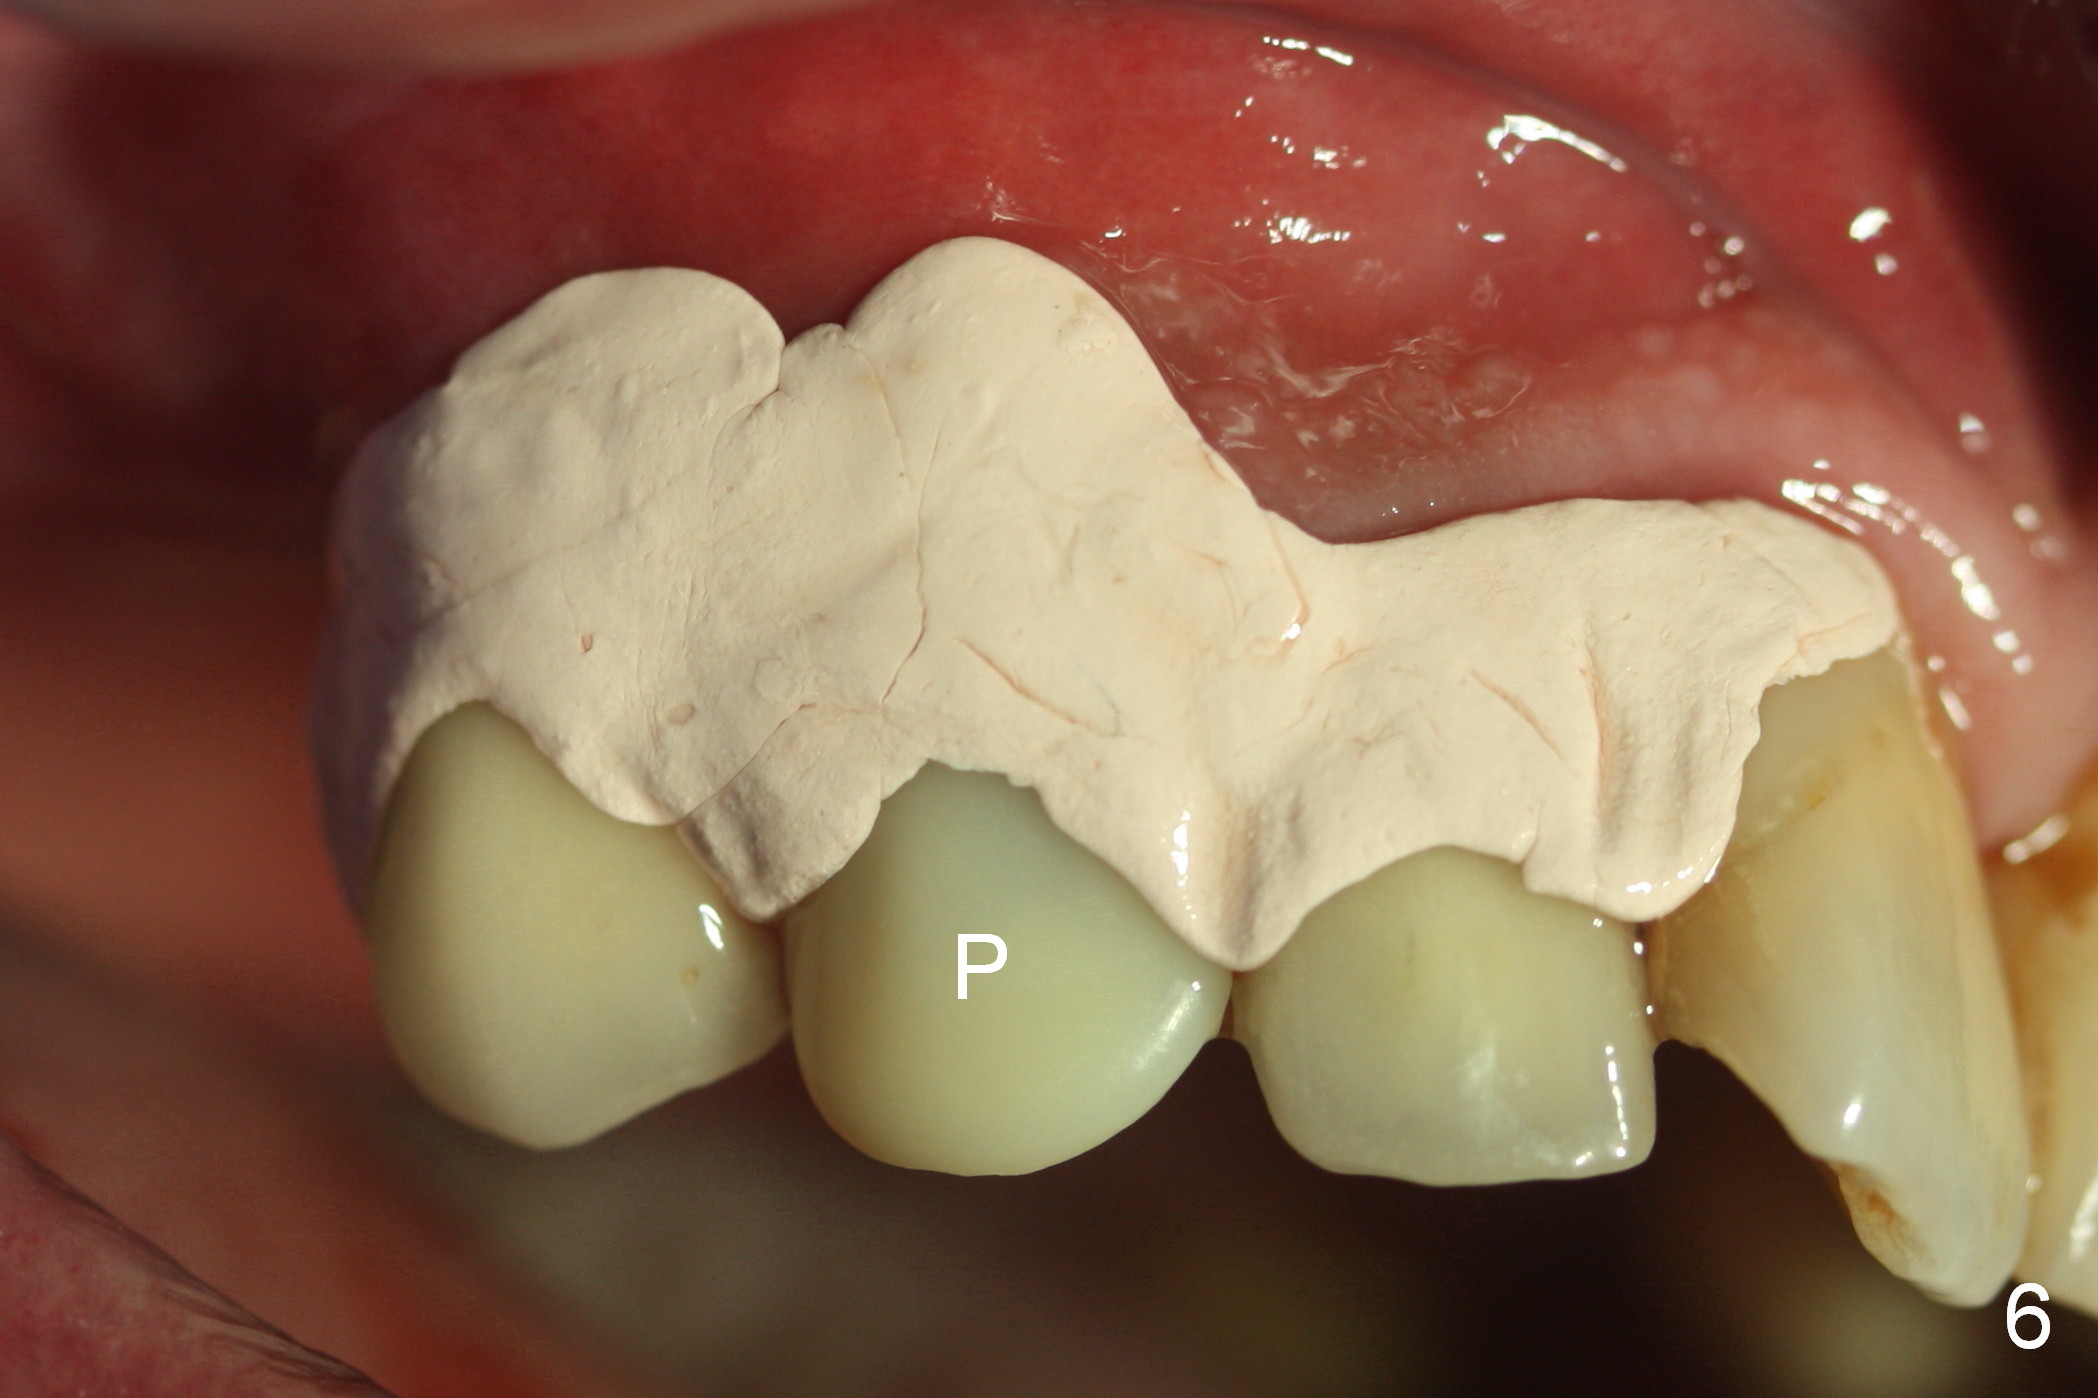

After extraction of the subgingival fractured upper right canine (Fig.1), the buccal plate is found to have been perforated at the apex. the root is measured 5x12 mm. Initial osteotomy with a 2 mm pilot drill shows that the bone is soft (Fig.2). After use of a 3.2 mm drill (underprep, normal drill size (3.7 mm)), a 4.5x15 mm implant is placed with insertion torque > 50 Ncm (Fig.3). The implant is further torqued until the implant plateau is 3 mm apical to the buccal gingival margin; a 5.5x5(3) mm abutment is placed (Fig.4,5 A). Osteogen plug is inserted into the apex of the socket, while the rest of gap is filled with mineralized cortical allograft and Osteogen. An immediate provisional (Fig.5,6 P) is fabricated to keep the graft in place, followed by periodontal dressing (Fig.6).

Three months postop, the provisional is dislodged (Fig.7-9). The mesial gingiva is hypertrophic buccally (Fig.8 *) and lingually (Fig.9 *). There appears to biologic width violation (Fig.5). The abutment should be changed to the one with smaller in diameter and longer in cuff (4.5x5(4) mm) with the buccal margin reduction.